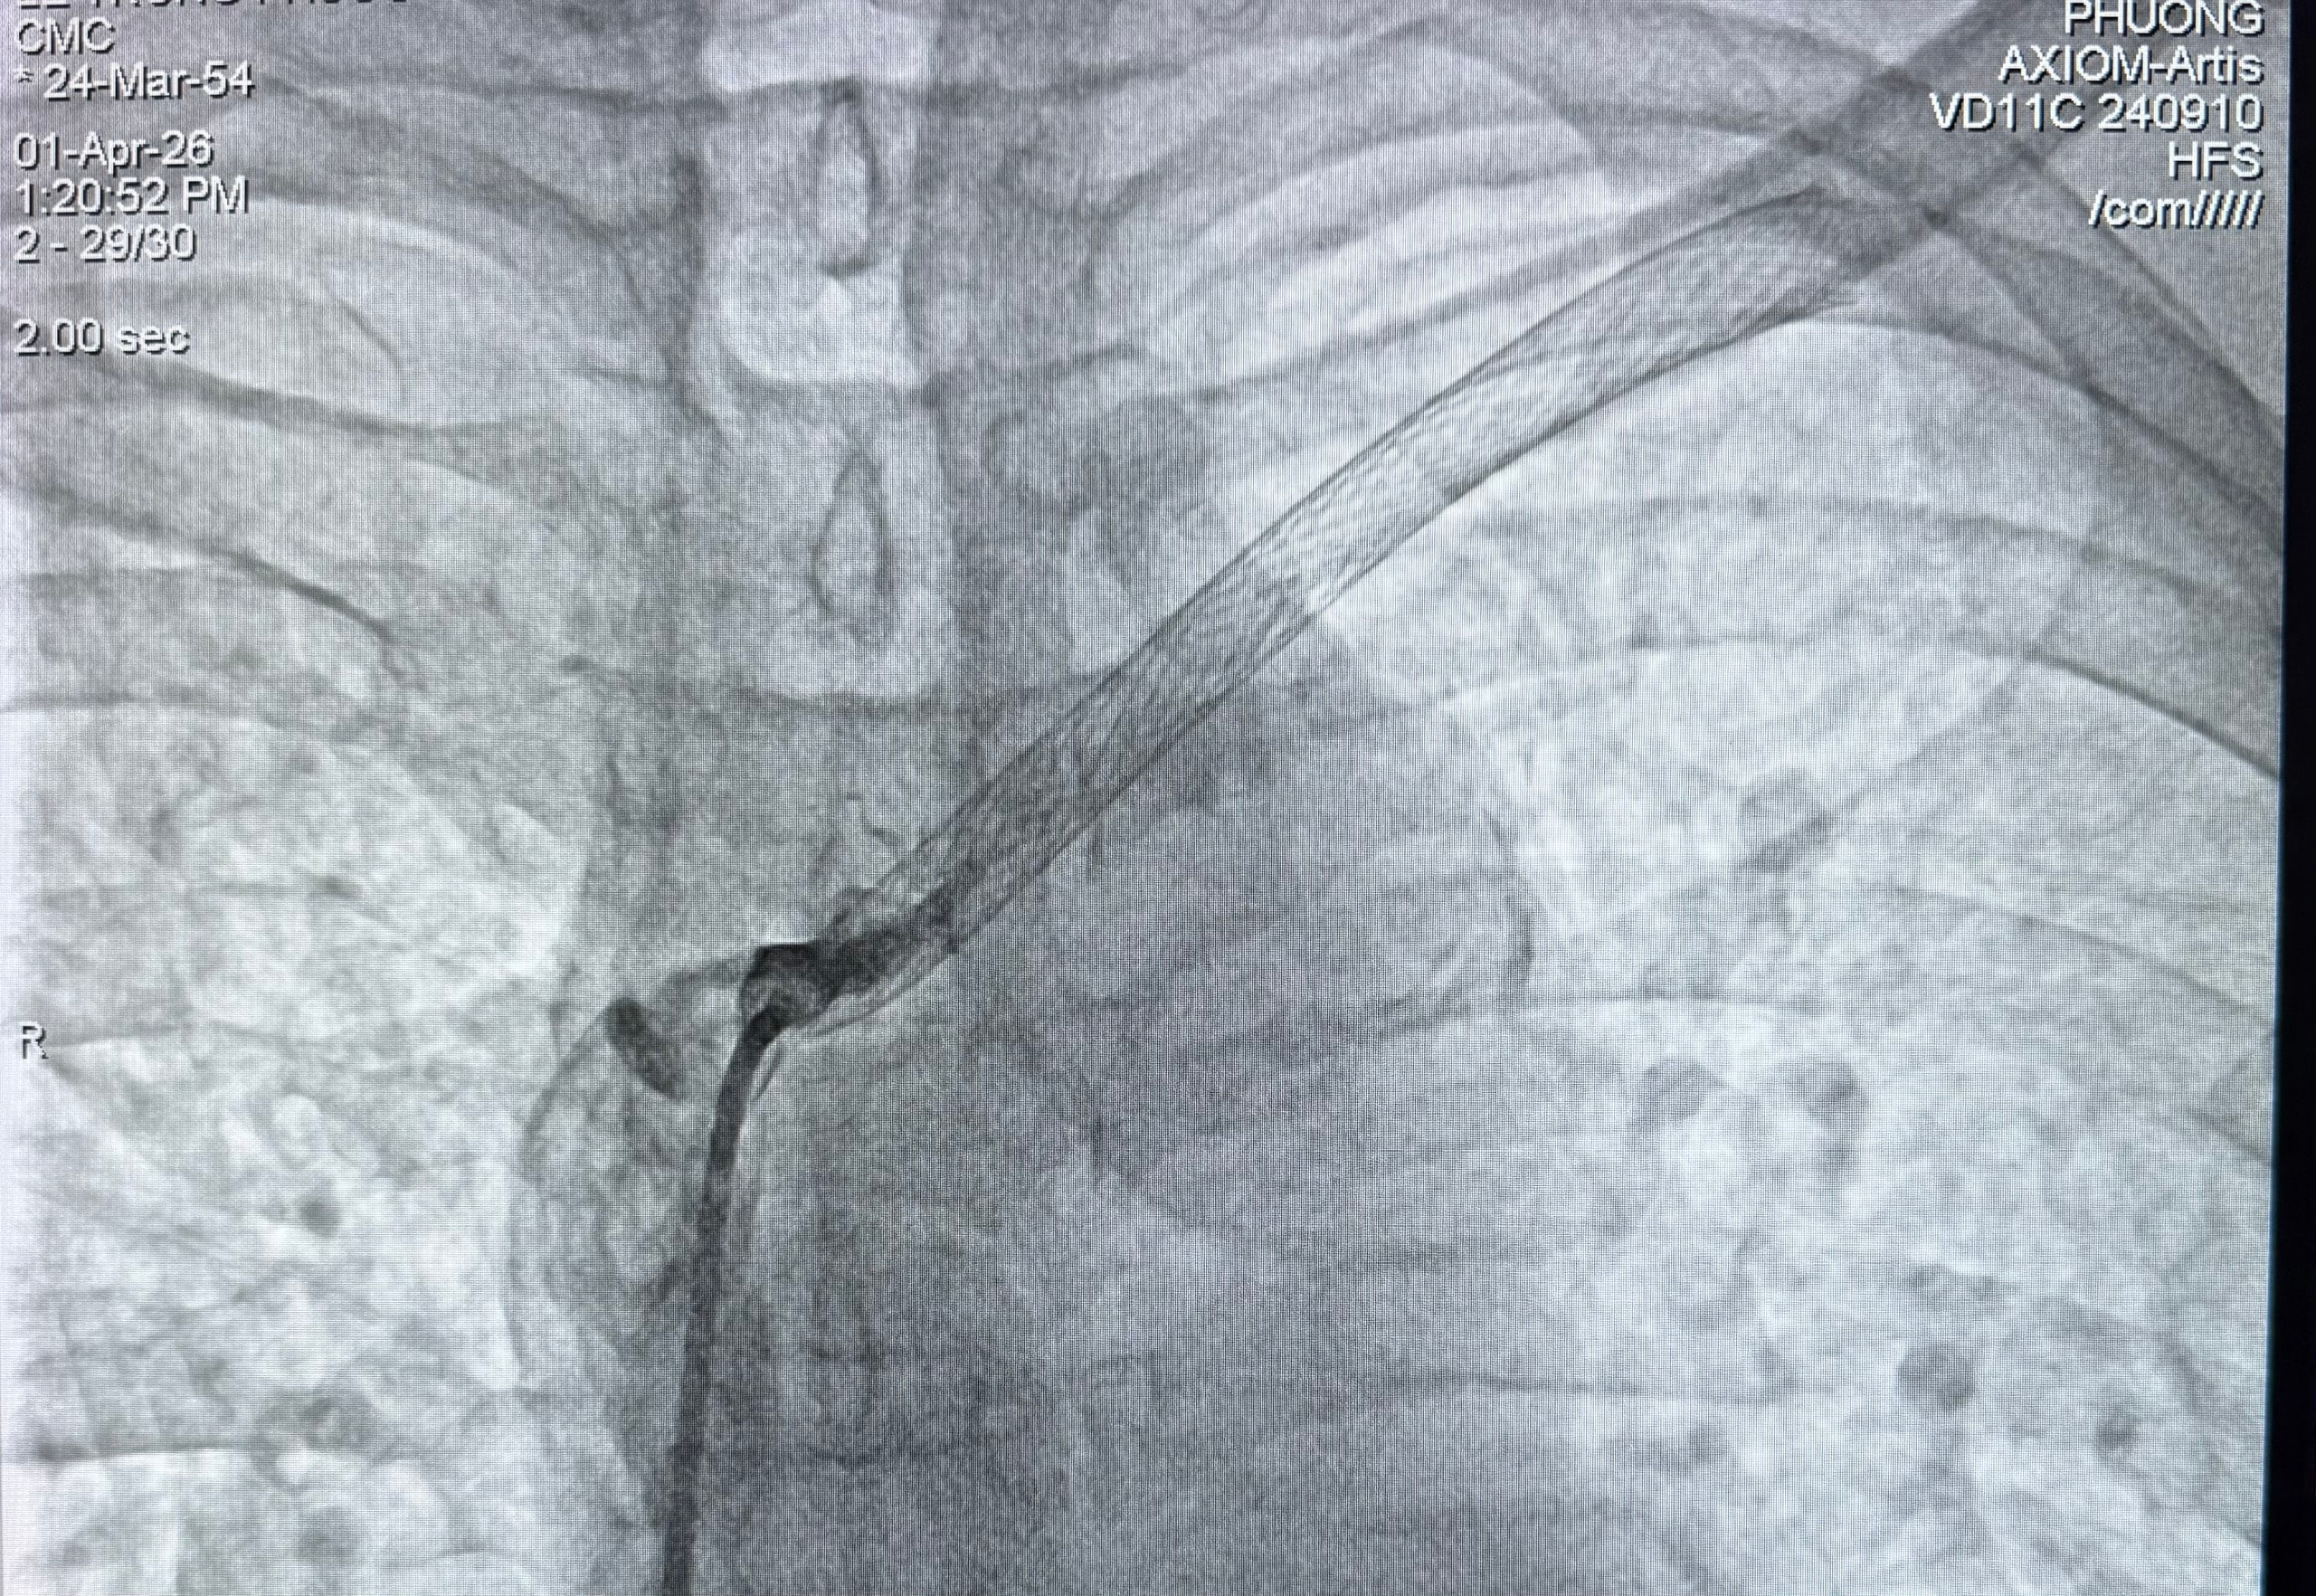

Tại Khoa Nội thận Lọc máu, qua hội chẩn liên chuyên khoa với Đơn vị Tim mạch Can thiệp, các bác sĩ xác định bệnh nhân bị tắc hoàn toàn trong stent cũ tại tĩnh mạch thân cánh tay đầu trái và tắc đoạn đầu tĩnh mạch đầu. Đây là nguyên nhân chính gây ứ trệ dòng máu trở về tim, dẫn đến tình trạng sưng đau kéo dài.

Bệnh nhân tắc hoàn toàn trong stent tĩnh mạch thân cánh tay đầu trái.

Ngày 1/4/2026, ekip can thiệp gồm TS.BS Hoàng Phương, BS Phạm Tấn Hoàng Long cùng các kỹ thuật viên đã tiến hành thủ thuật. Dưới hệ thống chụp mạch số hóa xóa nền DSA hiện đại của hãng Siemens, ekip đã thực hiện can thiệp qua da chỉ với gây tê tại chỗ. Sau gần 2 giờ đồng hồ tập trung cao độ, hai vị trí tắc hẹp hoàn toàn đã được khai thông, tái tạo dòng chảy thông suốt.

Dòng chảy được tái thông...